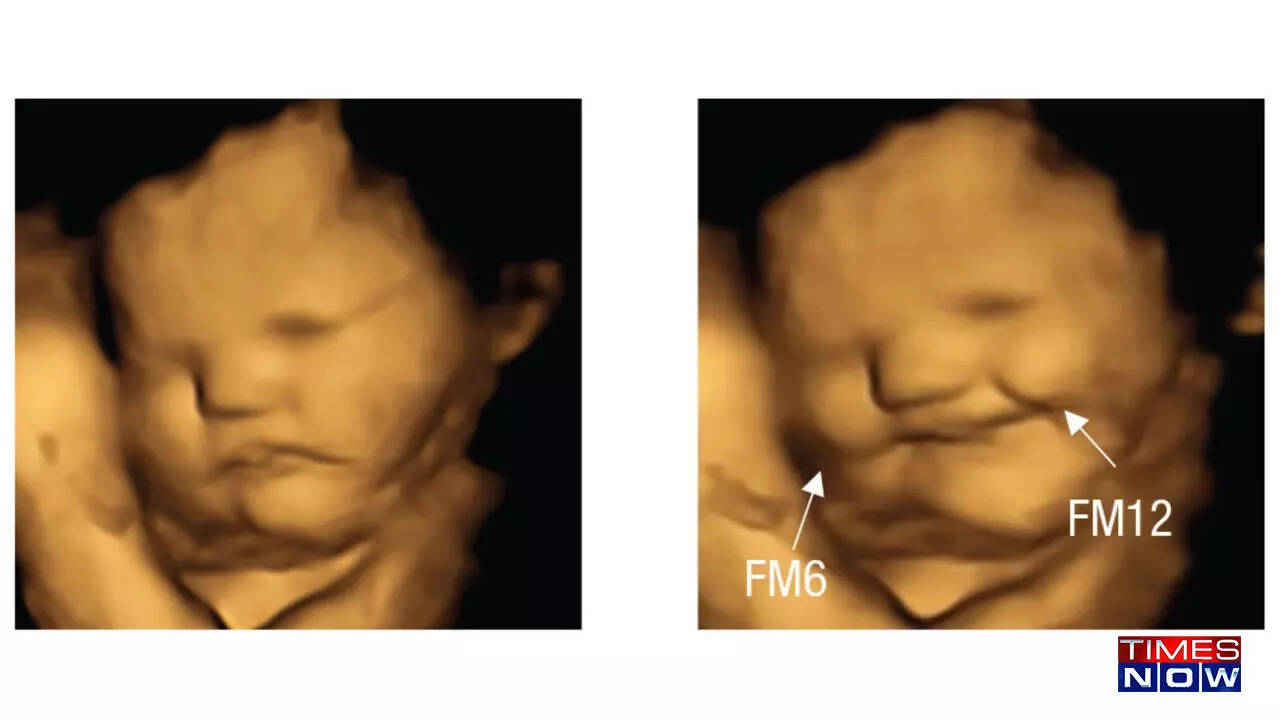

From www.timesnownews.com

4D ultrasound shows facial expressions of babies reacting to taste and Can Babies Smell In The Womb Yes, babies can pick up on smells in the amniotic fluid from their mother’s foods and the aromas she smells starting around 20 weeks. Your baby's sense of smell develops in the womb, and by the time they're born babies can smell about as well as adults. Our psychologists have shown the first direct evidence that babies react differently to. Can Babies Smell In The Womb.